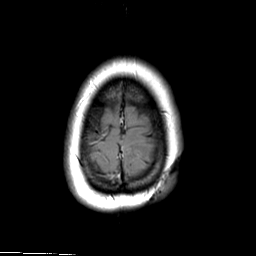

MR Study #3 -- Slice #47